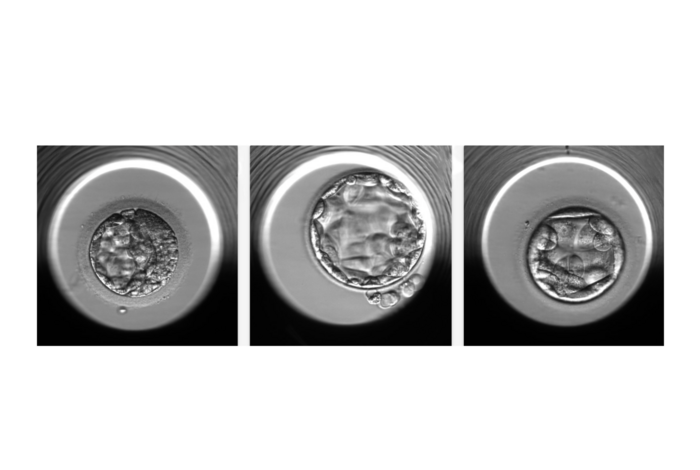

IMAGE: EXAMPLES OF EMBRYOS EVALUATED BY THE STORK-A ALGORITHM. FROM LEFT TO RIGHT, AN EMBRYO PREDICTED TO HAVE A NORMAL CHROMOSOME COUNT OR A SINGLE CHROMOSOMAL ABNORMALITY; AN EMBRYO PREDICTED TO HAVE A NORMAL CHROMOSOME COUNT; AN EMBRYO PREDICTED TO HAVE MORE THAN ONE CHROMOSOMAL ABNORMALITY. view more

Having an abnormal number of chromosomes, a condition called aneuploidy, is a major reason embryos derived from in vitro fertilization (IVF) fail to implant or result in a healthy pregnancy. One of the current methods for detecting aneuploidy involves the biopsy-like sampling and genetic testing of cells from an embryo—an approach that adds cost to the IVF process and is invasive to the embryo. The new algorithm, STORK-A, described in a paper published Dec. 19 in Lancet Digital Health, can help predict aneuploidy without the disadvantages of biopsy.  It operates by analyzing microscope images of the embryo and incorporates information about maternal age and the IVF clinic’s scoring of the embryo’s appearance.

The new STORK-A algorithm uses microscope images of embryos taken at five days past fertilization, clinic staff’s scoring of embryo quality, maternal age, and other information that is normally gathered as part of the IVF process. Because it uses AI, the algorithm automatically “learns” to correlate certain features of the data, often too subtle for the human eye, with the chance of aneuploidy. The team trained STORK-A on a dataset of 10,378 blastocysts for which ploidy status was already known.

From its performance, they assessed the algorithm’s accuracy in predicting aneuploid versus normal-chromosome “euploid” embryos at nearly 70 percent (69.3%). In predicting aneuploidy involving more than one chromosome—complex aneuploidy—versus euploidy, STORK-A was 77.6 percent accurate. They later tested the algorithm on independent datasets, including one from an IVF clinic in Spain, and found comparable accuracy results, demonstrating the generalizability of STORK-A.